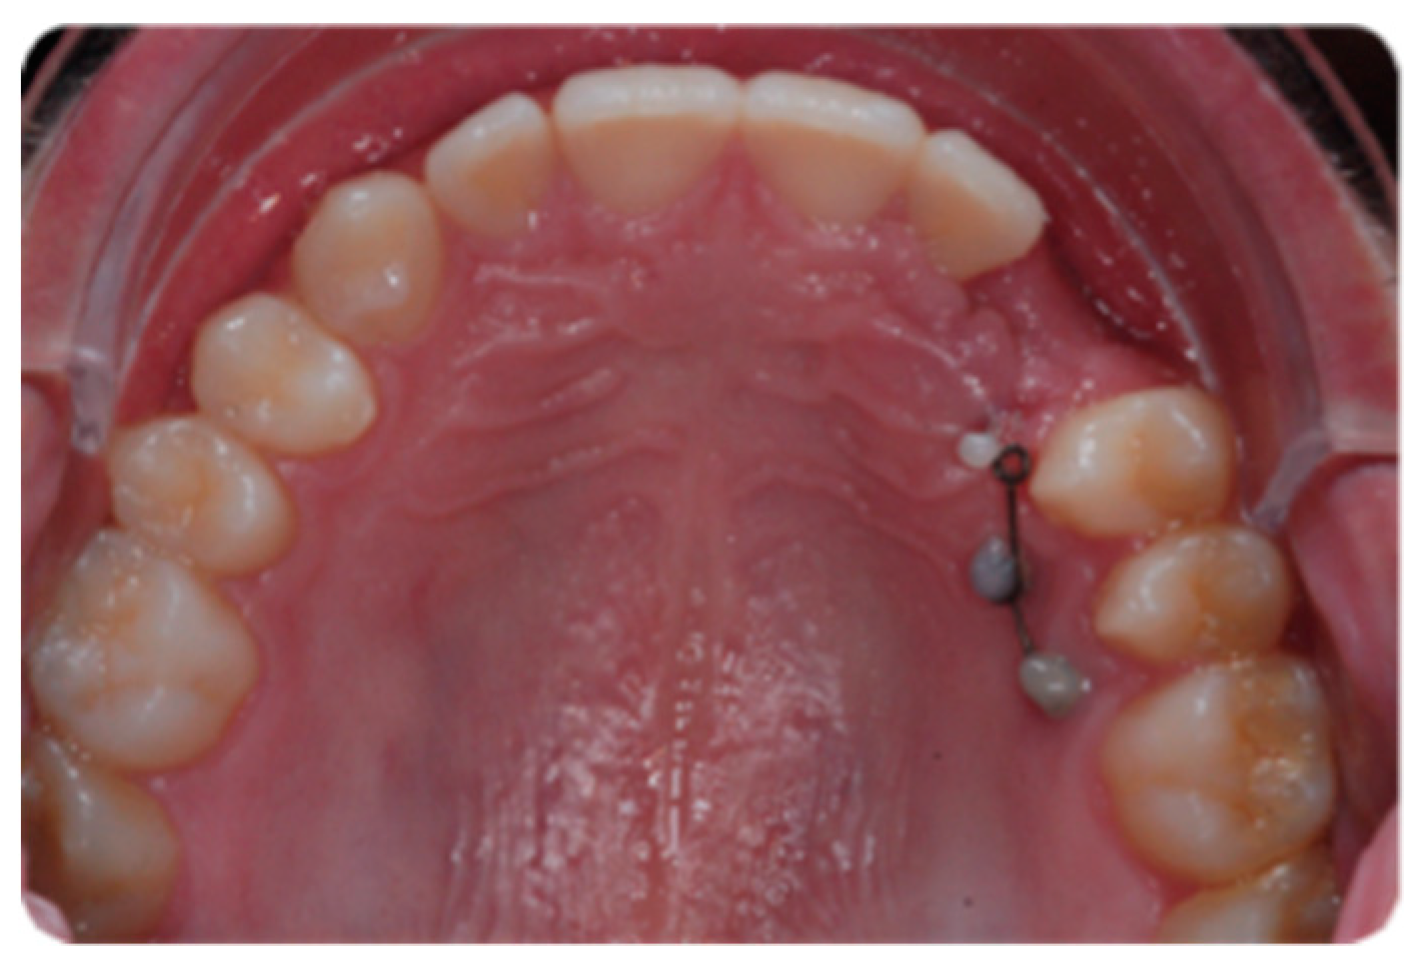

Figure 1 shows an initial stage of treatment—the upper arch with the absence deciduous canine no. 63. The malposition of the teeth, such as distorotation of the incisors, vestibuloposition of the right canine, as well as an irregular and incorrect shape of the upper arch, are noticeable.

Figure 1.

Pre-treatment records of the first patient.